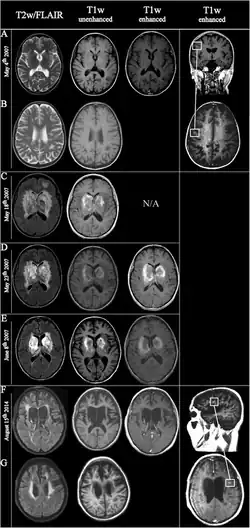

.png)

The pathology of ADEM is very similar to that of MS with some differences. The pathological hallmark of ADEM is perivenous inflammation with limited "sleeves of demyelination".[54][14] Nevertheless, MS-like plaques (confluent demyelination) can appear[55]

Plaques in the white matter in MS are sharply delineated, while the glial scar in ADEM is smooth. Axons are better preserved in ADEM lesions. Inflammation in ADEM is widely disseminated and ill-defined, and finally, lesions are strictly perivenous, while in MS they are disposed around veins, but not so sharply.[56]